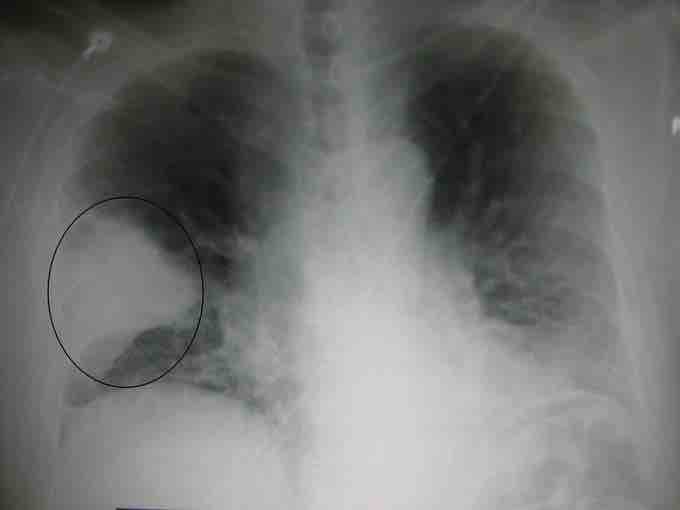

A chest X-ray showing a very prominent wedge-shaped bacterial pneumonia in the right lung.